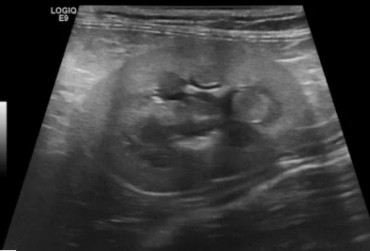

Określenie „rozpoznanie cioci Minnie” pochodzi ze Stanów Zjednoczonych i jest żartobliwym określeniem rozpoznania patognomonicznego, stosowanym głównie przez radiologów. Zwrot ten stał się popularny w latach 90. XX w. za sprawą strony internetowej o takim tytule. Obecnie to określenie stosuje się również w metodologii nauczania klinicznego. W artykule przedstawiono przypadki rozpoznań „cioci Minnie” z własnego archiwum ultrasonografii jamy brzusznej małych zwierząt.